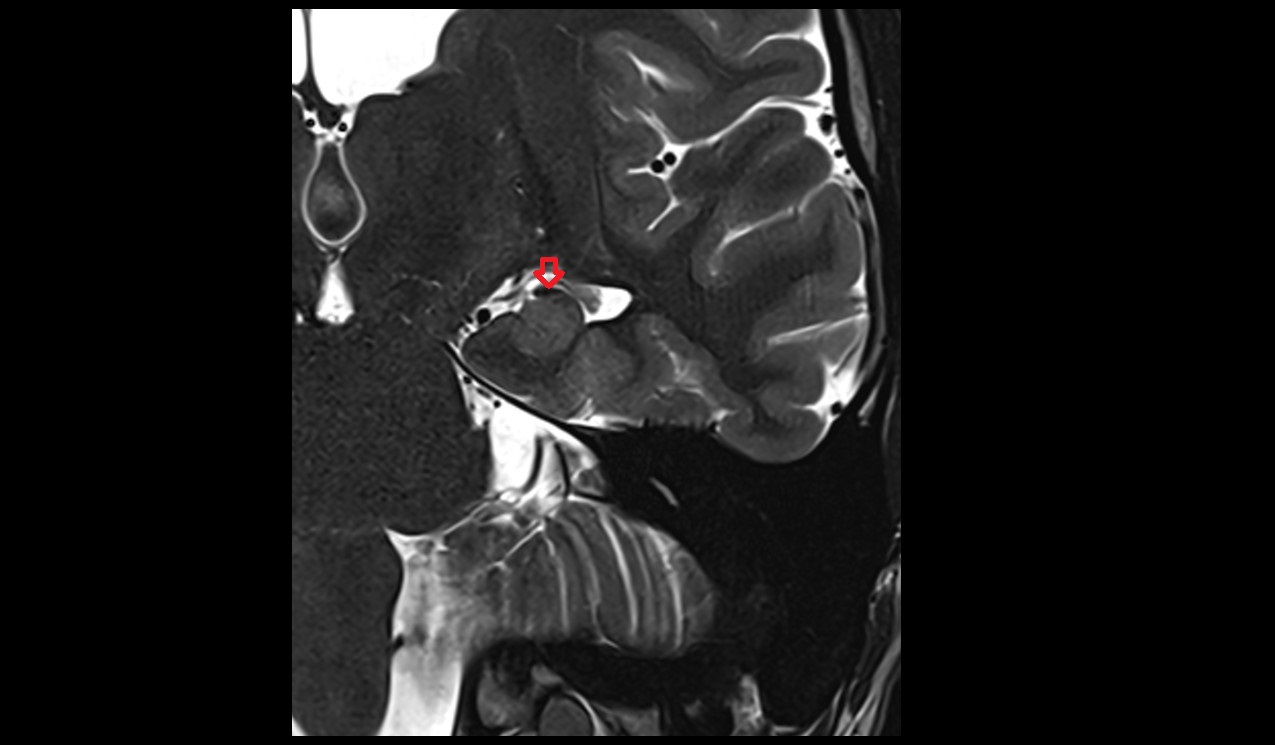

- Temporomandibular joint

- Articular disc of temporomandibular joint

- Articular eminence

- Mandibular condyle

- Mandibular fossa